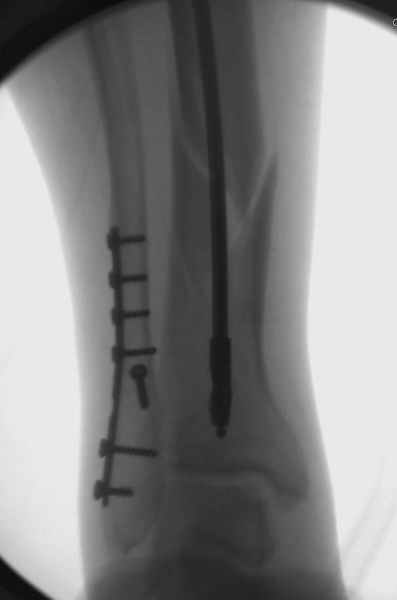

У меня молодой врач на линии, снимки отправил через эл. почту,

спрашивает что делать с больным который поступил недавно, фермер 55 лет падение при пьяной драке в баре, года два назад перенес операцию на лодыжке, на снимках и КТ перелом без вовлечения сустава,

Повреждение такой локализации, на которой применимы и аппарат (классический Илизарова или гибридный), пластина, особенно Locked Plate, и гвоздь с блокированием. В нашей клинике был бы выполнен закрытый интрамедуллярный остеосинтез. Желательно использовать гвоздь с возможностью провести более чем 2 обычных фронтальных винта в дистальном отломке.

Здесь мы использовали новый Synthes Nail с дополнительными дырками, в проксимальной части 4: по две косых и поперечные (один стандартный а другой динамический), в дистальной части две поперечные, прямая и косая. Вес больного более 120 кг, нагрузку начнем через месяц.

Получилось красиво, поздравляю. Вверху можно было ограничиться одним винтом во фронтальное статическое отверстие, зачем два 45-градусных?

При такий спирали задний край tibia может быть сломан - нет ли этого в данном случае? На всякий случай можно было ввести 1-2 винта 4,5 мм спереди назад мимо гвоздя. Хотя самый дистальный блокирующий винт, возможно, зацепил этот отломок. А какой тут диаметр гвоздя и locking винтов?